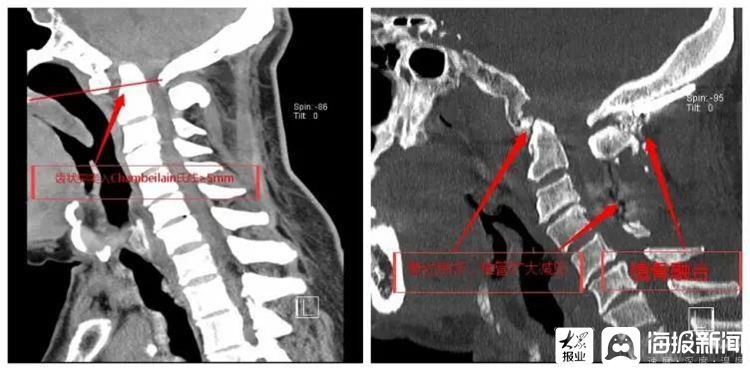

手术前后CT对比